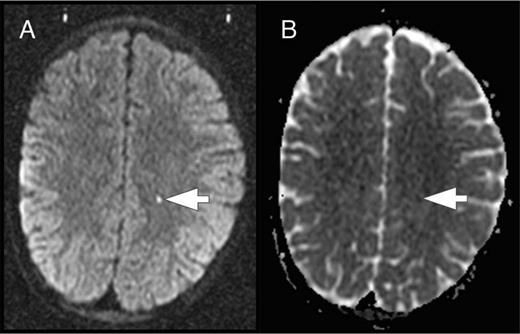

The brain is at constant threat of ischemic injury in sickle cell disease (SCD). The risk of overt stroke for children with SCD is more than 200 times higher than that for the general population, and this burden of overt stroke continues well into adulthood. An even more common form of neurologic injury in SCD is silent cerebral infarction (SCI), which has a prevalence of up to 40%. SCI refers to generally small, permanent brain lesions that are not associated with obvious focal neurologic signs (Figure 1). The term SCI is a misnomer because these strokes, even though they do not produce focal or localizing signs on neurologic examination, are often not “silent.” SCI is a morbid condition associated with neurocognitive impairment, poor academic performance, neurologic soft signs, and increased risk for subsequent overt stroke. Covert cerebral infarction may be a better descriptor, but SCI is the accepted term.

SCI. Two typical SCI lesions (arrows) are shown in the frontal and deep white matter in a T2-weighted magnetic resonance image of the brain in a child with sickle cell anemia.

The definition of SCI has 2 components: (1) an infarct-like lesion on MRI of the brain and (2) a normal neurologic examination or no abnormality on neurologic examination that can be explained by the location of the infarct-like lesion. Specific definitions of the SCI lesion on MRI vary by study, but the Silent Cerebral Infarct Transfusion (SIT) Trial (www.ClinicalTrials.gov identifier #NCT00072761) rigorously defined it to be an MRI signal abnormality (increased signal) of at least 3 mm in 1 dimension that was visible on at least 2 views of T2-fluid-attenuated inversion recovery images of the brain.1 Because SCI is clinically covert, it must be identified by screening MRI of the brain. SCI is therefore almost always identified incidentally as a remote event well after its onset, which makes the study of its causes and frequency quite challenging. The goal of this chapter is to highlight several of the recent advances in our understanding of the frequency, risk factors, correlates, causes, and management of SCI.